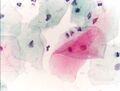

صورة مجهرية لمسحة عنق الرحم عادية